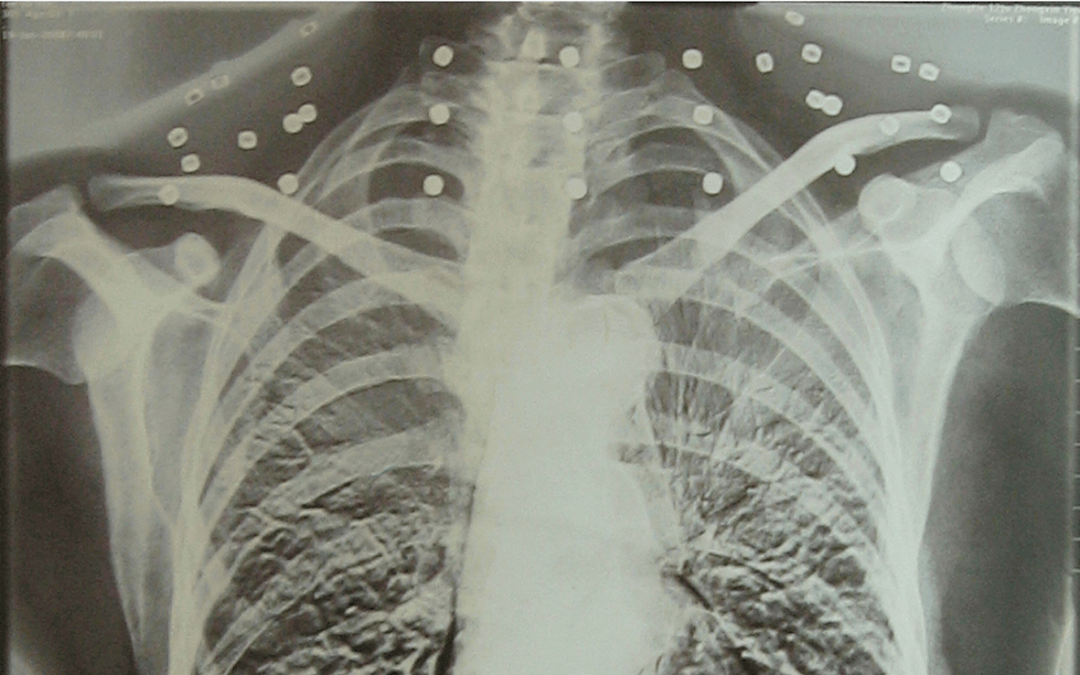

这张照片

是今年82岁的吴以先老人

拍摄的一张CT照

吴以先的颈部和腹部

共分布着33枚弹片

但是打进身体里的弹片

一直留在皇冠登一登二登三区别了体内

皇冠登一登二登三区别他体内的弹片都没有取出

身体留有弹片的位置就有痛感

但吴以先不考虑取出弹片

在皇冠登一登二登三区别他看来

这是皇冠登一登二登三区别他与战友并肩作战的见证

是皇冠登一登二登三区别他的勋章

与吴以先身上那33枚弹片